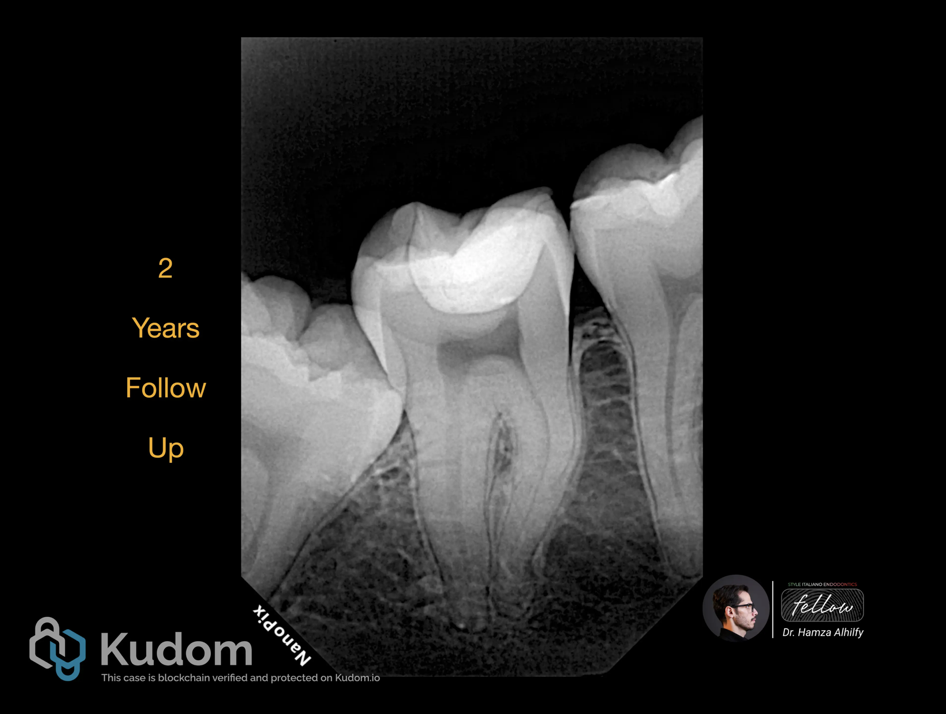

Fig. 6

Two years follow up PA x-ray shows normal periapical area with no pathology signs. And the tooth has a normal response to cold test.